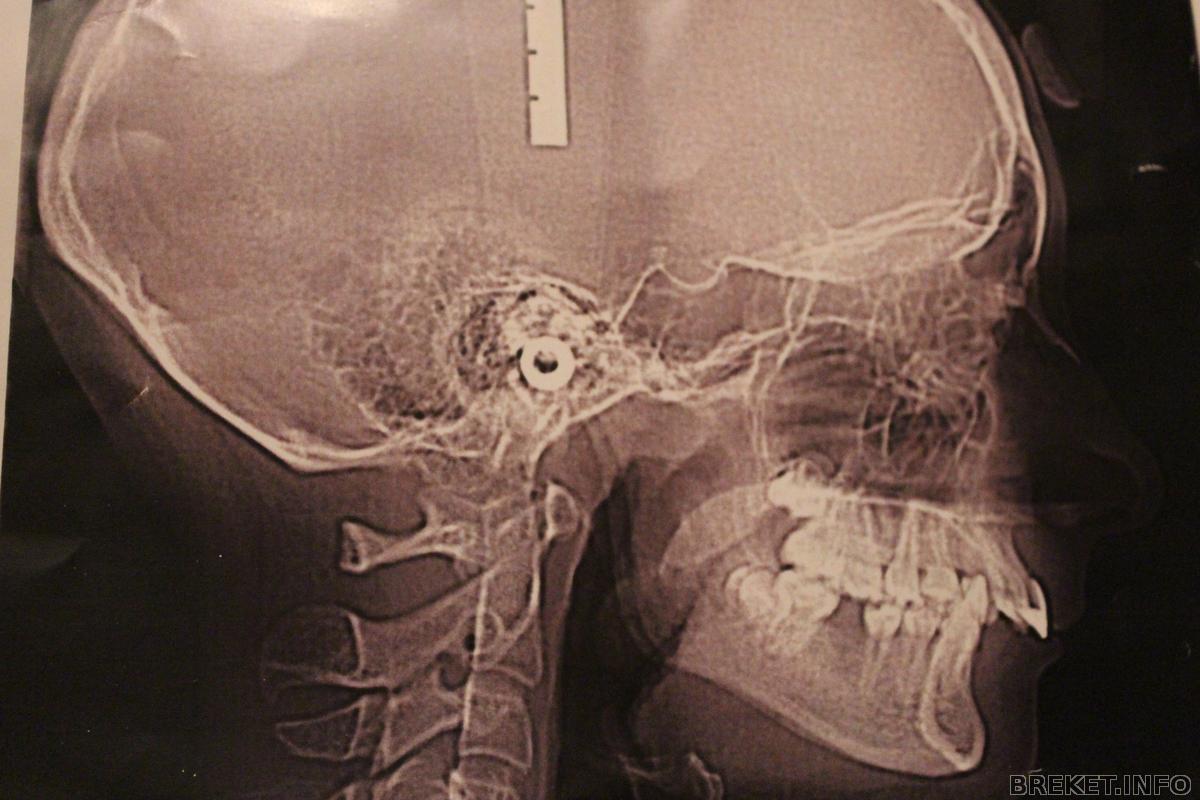

Немного расскажу о своей проблеме ![]()

Мне поставили БС потому , что у меня дистальный прикус.Искривление зубов есть только на НЧ и то несколько зубов.А остальные ровные...Но они вылезли вперед

Смотрю на снимок, и не могу определить существенные отличительные детали.. у меня так же глубоко прячется нижняя челюсть, разве что в небо так не втыкается, и наклон передних почти отсутствует (что собсна счас и исправляем).. А в остальном (прекрасная маркиза, все хорошо ла ла ла ла)) не вижу отличий.. Дистальный=глубокий???

BlackJecky, мне кажется, что у глубокого НЧ задвинута за ВЧ, а у дистального еще и наклон у ВЧ

дистальный это когда вот так

а глубокий это когда челюсть верхняя почти полностью перекрывает нижнюю

характеризуется чрезмерным выступанием верхней челюсти над нижней, там просто дырень

ты бы показала фото в прикусе, а то сейчас не понятно насчет дисталки